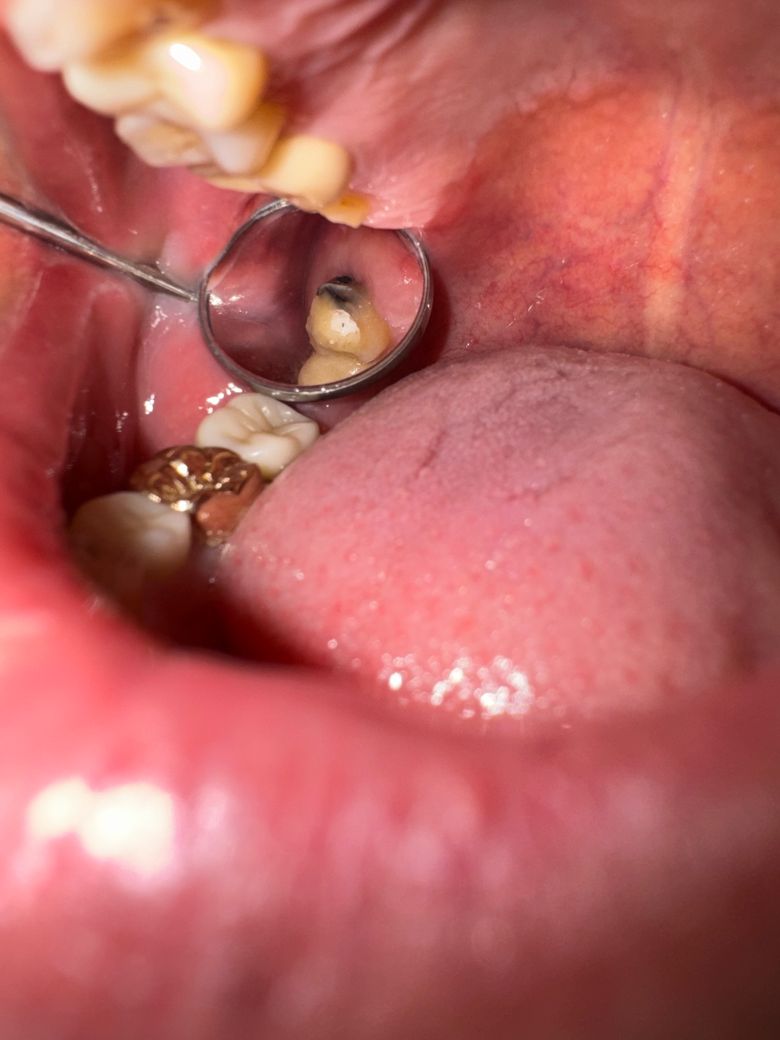

충치인지아닌지 봐주세요 크라운을씌울라고하셔서..

신경치료다하고 이제 다음주에 본뜬데서 한번 저녁에보니

안쪽은 이렇게 충치처럼 잇는데 이거치료안하고 바로 크아운싀워두되는건가요? 이걸왜 방치해둔지 모르겠어요

착색이라기엔 두꺼워보이는데 조언부탁드려요

해당 사진은 아직 치아를 본뜨기 전에 다듬지 않은 사진으로 보여집니다. 본뜨기 전에 마취를 하고 치아를 적절히 깍는데 이때 아마 해당 부분을 제거할 것으로 보입니다. 즉 현재 사진처럼 되어 있더라도 본뜨기 전에는 치아를 깍으면서 해당 부분이 제거될 것이니 걱정하지 않으셔도 됩니다.

사진에 보이는건 충치가 잇는것같습니다. 크라운 씌우기 전에 제거를 하고 레진으로 다시 채울꺼에요.

사진으로 봤을 경우에는 지대치 뒤쪽으로 충치가 있는 것으로 보입니다. 충치가 있다면 해당 부위를 제거하고 치과형 제대로 충전을 한 뒤 보철 치료를 하는 것이 좋습니다.